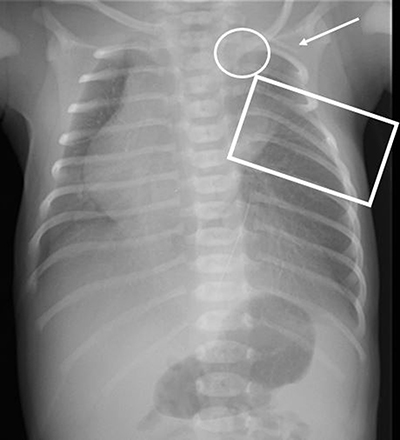

Figure 2

Chest X-ray at day 0 shows 11 ribs on the right side and 11 ribs plus an apparent cervical rib on the left side (white arrow). The intercostal spaces between ribs 4 and 6 on the left side appear narrowed (rectangle). The medial end of the left clavicle (circle) has an abnormal low position compared to the right clavicle and the cardiac silhouette is positioned on the right side.